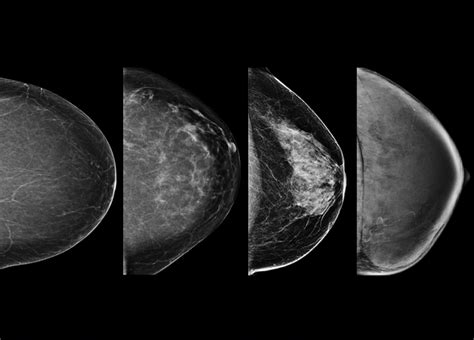

For decades, standard 2D digital mammography was the gold standard. However, 2D images take a flattened view of the entire breast, which can lead to overlapping tissues that look like suspicious spots. A Dense Breasts 3D Mammogram, clinically known as digital breast tomosynthesis, works differently by taking multiple images from various angles. These images are then reconstructed into a series of thin “slices,” allowing the radiologist to scroll through the breast tissue layer by layer.

Imaging Style Single flattened image Layered, multi-angle images

Accuracy for Dense Tissue Lower (potential masking) Higher (see through layers)